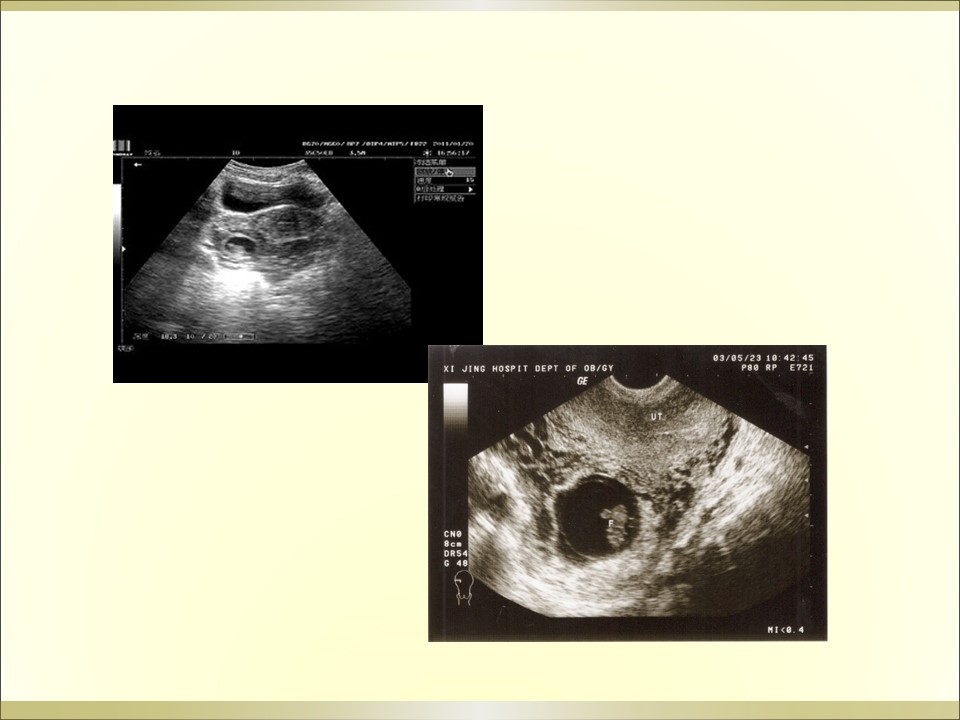

妇产科急腹症是指因妇科疾病引起的剧烈的急性腹痛,可以是原有疼痛突然加剧,或原无疼痛突然发生,是病因较多的常见病,特点是发病急、病变进展快、病情重,需要及时作出病因诊断及治疗。